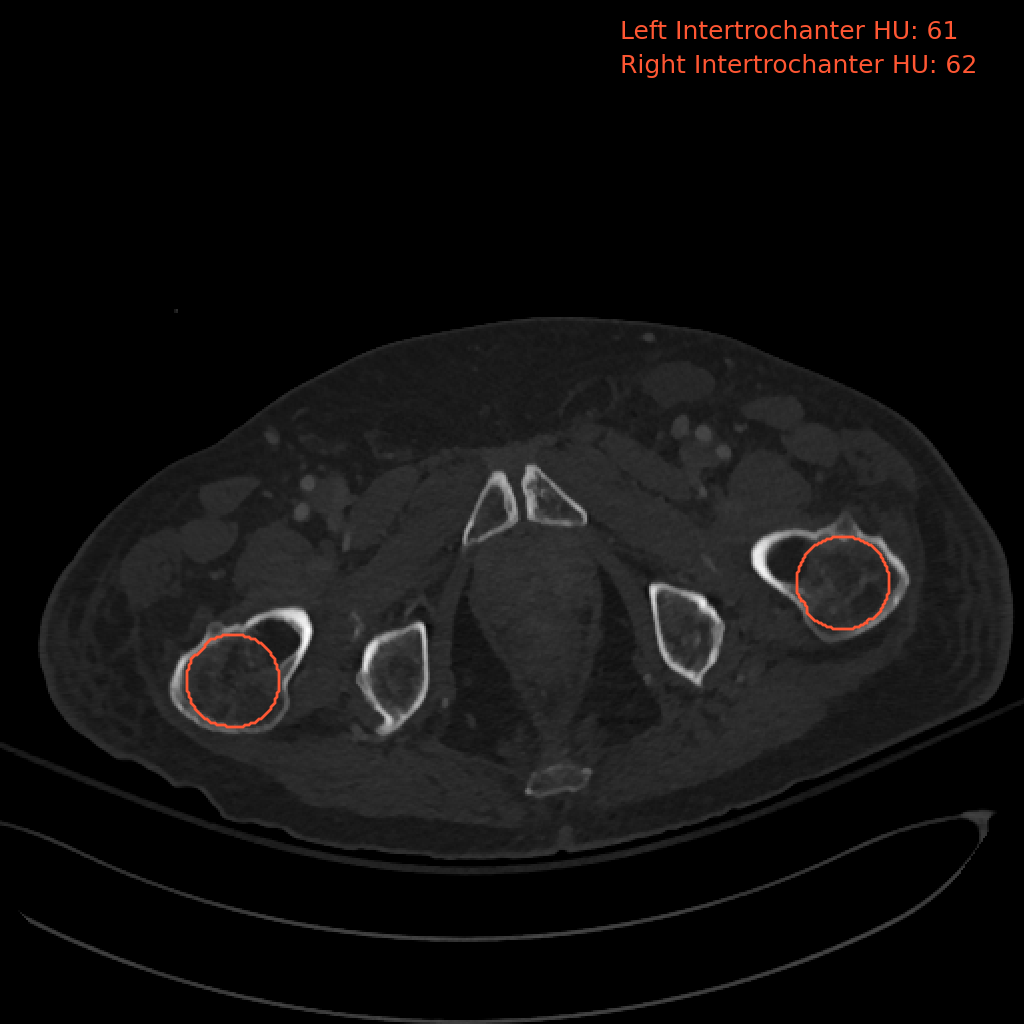

## 3D Analysis of the Femur

### Usage

```bash

bin/C2C hip -i

```

- input_path should contain a DICOM series or subfolders that contain DICOM series.

### Example Output Image